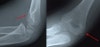

영상 검사

단순 AP 및 Lat 사진으로 확인 가능하나 Both oblique까지 찍는 것이 좋습니다.

성인에서는 소아 골절과는 달리 대개의 경우 전이가 적습니다.

X-ray : 과상 골절(Supracondylar fracture)